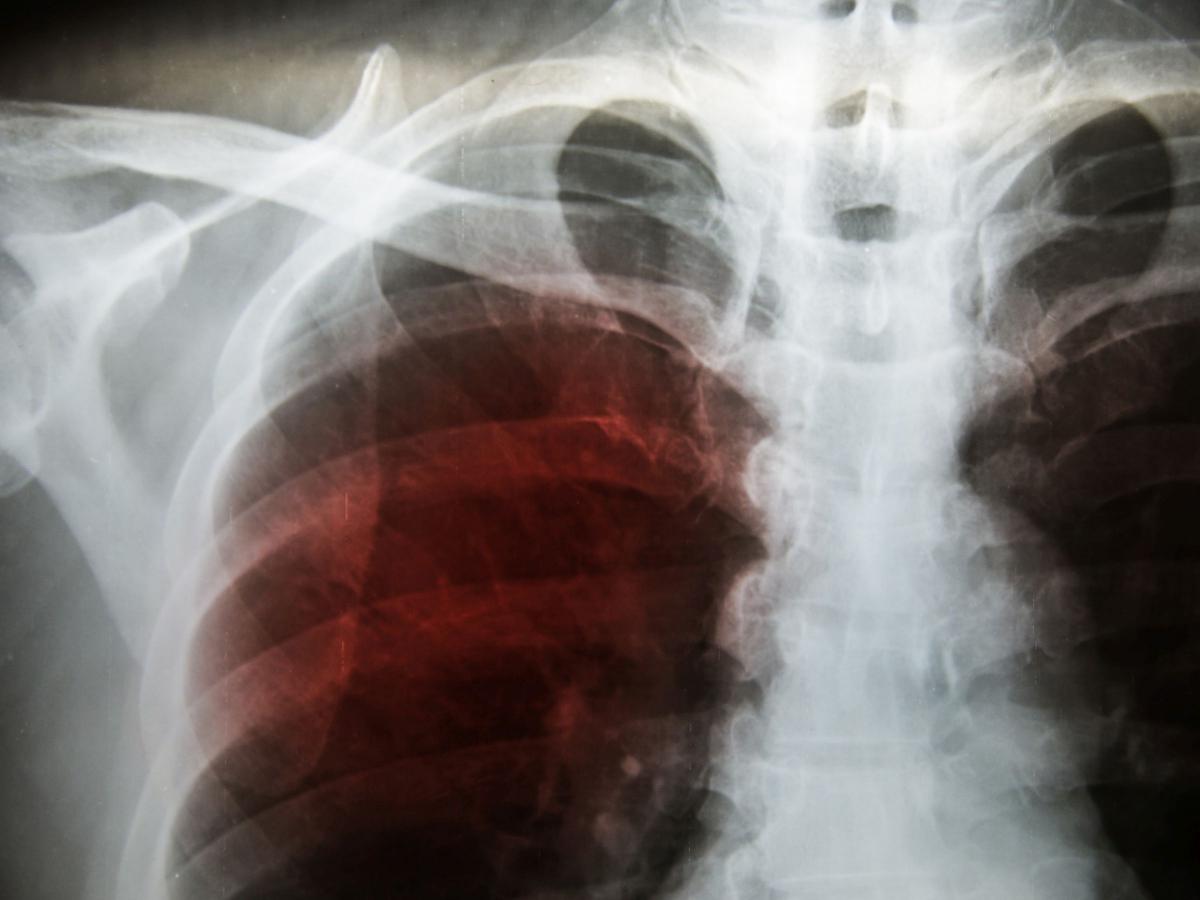

Nel decennio 2010-2020, sono stati registrati in Italia 16.993 decessi a causa del mesotelioma maligno, il tumore maggiormente associato all’esposizione all’asbesto. Questa patologia ha colpito soprattutto gli uomini, con 12.276 casi rispetto ai 4.717 riscontrati nelle donne.

Un aspetto particolarmente significativo affrontato dal rapporto ISS è la possibile connessione tra l’esposizione all’amianto e altre forme di tumore, oltre al mesotelioma. In Lombardia, si stima che circa il 30% dei decessi per tumore ovarico sia collegato all’asbesto, specialmente nei comuni vicini a industrie che ne facevano largo uso.

Questo collegamento è particolarmente rilevante perché evidenzia come le problematiche sanitarie legate all’amianto possano estendersi oltre le patologie classiche, come il mesotelioma e i tumori polmonari, colpendo anche il sistema riproduttivo.